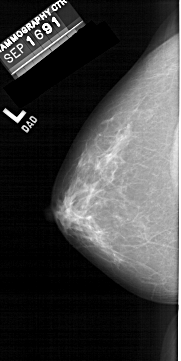

A_1456_1.LEFT_CC

LEFT_CC LINES 6136 PIXELS_PER_LINE 3076 BITS_PER_PIXEL 12 RESOLUTION 43.5 NON_OVERLAY